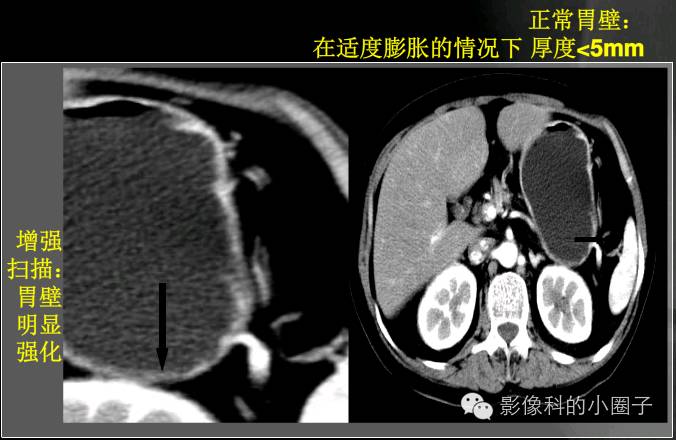

ct诊断误区胃窦壁增厚的诊断难点及误区这几点千万注意

胃壁增厚疾病ctmri影像表现

编者注:消化道ct检查重点是要解决消化道管壁显影,在空腔脏器的容积